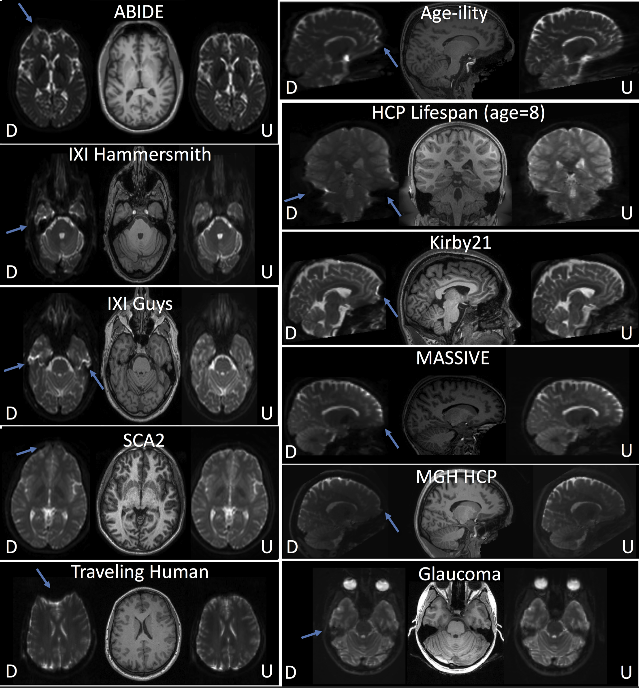

Corrected images created with data from open-sourced studies. The distorted (“D”) and undistorted (“U”) images are shown alongside T1 images. In all cases, effective distortion correction is visually apparent (distortions indicated by arrows). (Schilling, Bennett, et al.).